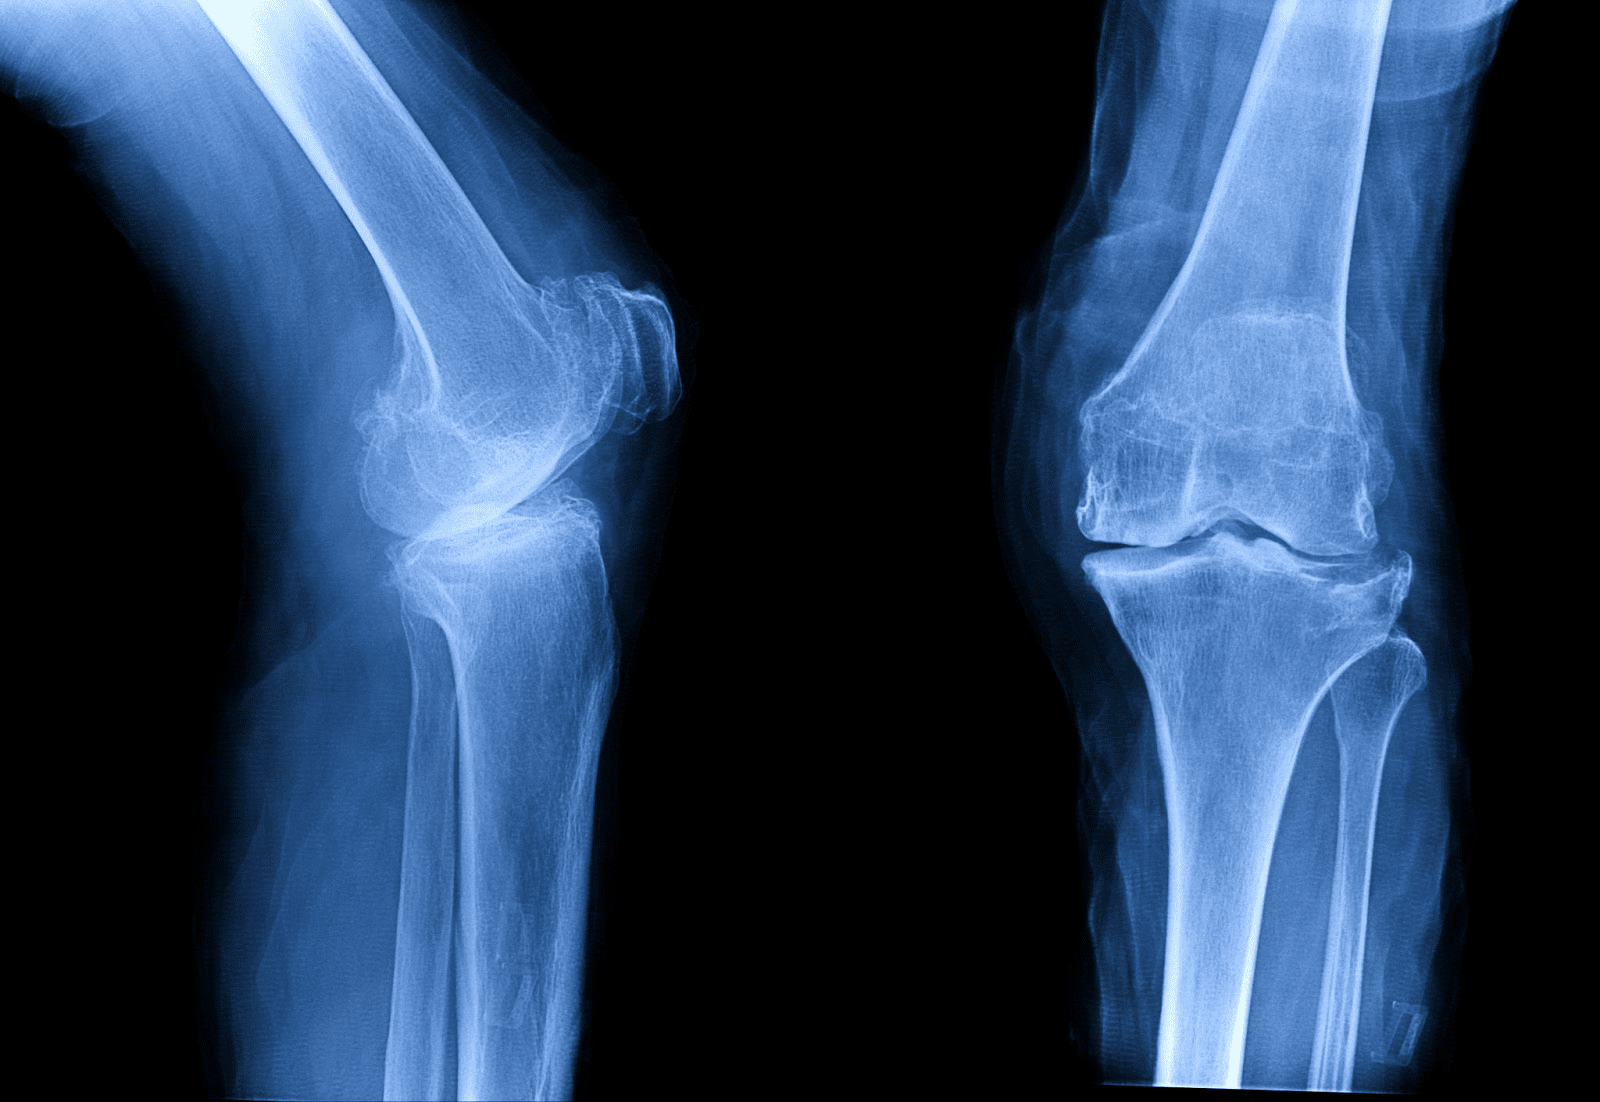

中國科學家團隊近日公佈一項突破性的醫療發明,名為Bone-02的骨骼膠水,能夠在短短三分鐘內修復骨折,有望徹底改變骨科手術的未來。這項研究由浙江省邵逸夫醫院(Sir Run Run Shaw Hospital)的林賢豐博士(Dr. Lin Xianfeng)領導,其靈感來自於牡蠣在潮濕且動態的表面上依然能牢固附著的非凡能力。與傳統的金屬植入物不同,Bone-02具有生物可吸收性,會隨著骨骼的自然癒合過程逐漸溶解,從而免除了患者需要接受第二次手術以移除固定物的痛苦與風險。目前,該黏合劑已在超過150名患者身上成功進行試驗,即使在血液豐富的複雜環境中,也展現出令人印象深刻的強度、安全性與快速黏合效果。

Bone-02的臨床試驗已涵蓋超過150名患者,並取得了令人鼓舞的成果。參與試驗的醫生報告指出,以往需要使用鋼板和螺釘的複雜手術,現在僅需過去一小部分的時間即可完成。除了速度上的優勢,該黏合劑還表現出強大的物理性能,其剪切強度達到0.5兆帕(MPa),抗壓強度約為10兆帕,足以媲美標準的金屬植入物。更重要的是,人體對Bone-02的耐受性良好,未出現重大的安全疑慮。這些發現表明,它有潛力在全球醫院中取代許多傳統的骨折固定方法,並對急診醫學產生深遠影響。

可吸收設計顛覆傳統骨科治療